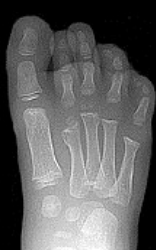

What disease is this? | Rheumatoid arthritis |

What disease is this? | Psoriatic arthritis |